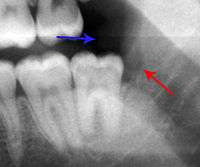

The periodontal ligament becomes inflamed and there may be pain when biting or tapping on the tooth. On an X-ray, bone resporption appears as a radiolucent area around the end of the root, although this does not manifest immediately.[9]:228 Acute apical periodontitis is characterized by well-localized, spontaneous, persistent, moderate to severe pain.[4]:125–135 The alveolar process may be tender to palpation over the roots. The tooth may be raised in the socket and feel more prominent than the adjacent teeth.[4]:125–135

- Radiographs utilized to find dental caries and bone loss laterally or at the apex.